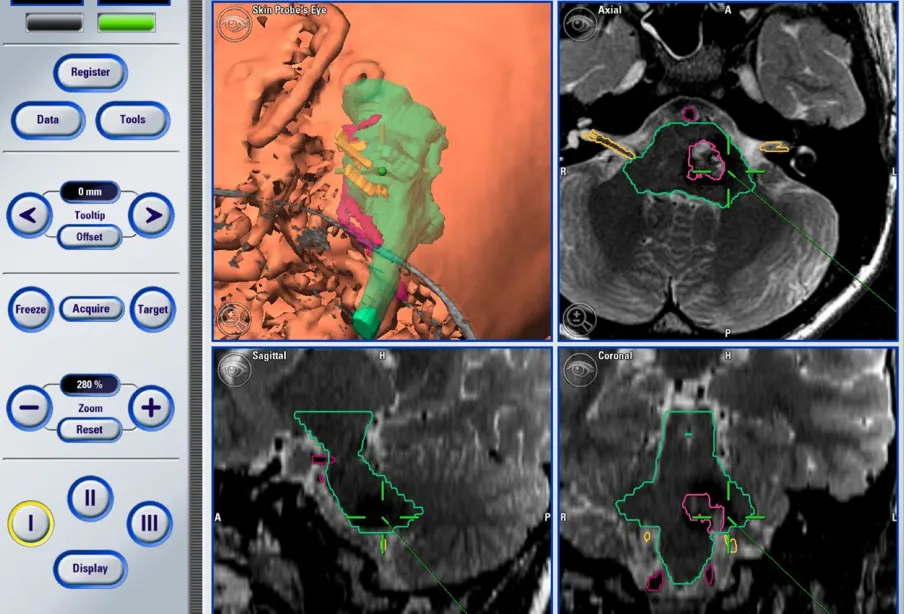

术前检查时,三维重建影像清晰显示:Rita的海绵状血管瘤与脑干核团、颅神经紧密缠绕——这也解释了她为何会出现“重影”“肢体无力”:病变已经压迫到控制视觉和运动的神经。

术前MR,发现脑干海绵状血管瘤,伴有脑出血。